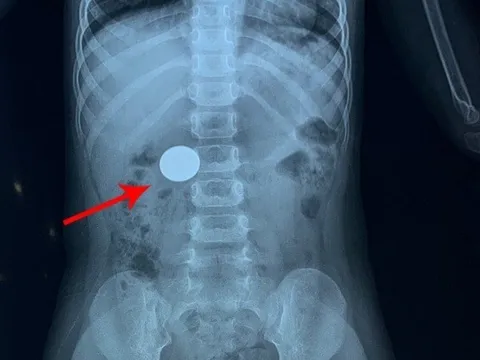

Phú Thọ: Thiếu niên phải nhập viện cấp cứu do nuốt phải hạt mít

Bệnh nhân T.Y.N (17 tuổi, trú tại xã Trung Sơn, huyện Yên Lập) đã nhập viện trong tình trạng buồn nôn, nôn nhiều. Theo người nhà của N, nguyên nhân là do N đã ăn mít, không may nuốt cả hạt.